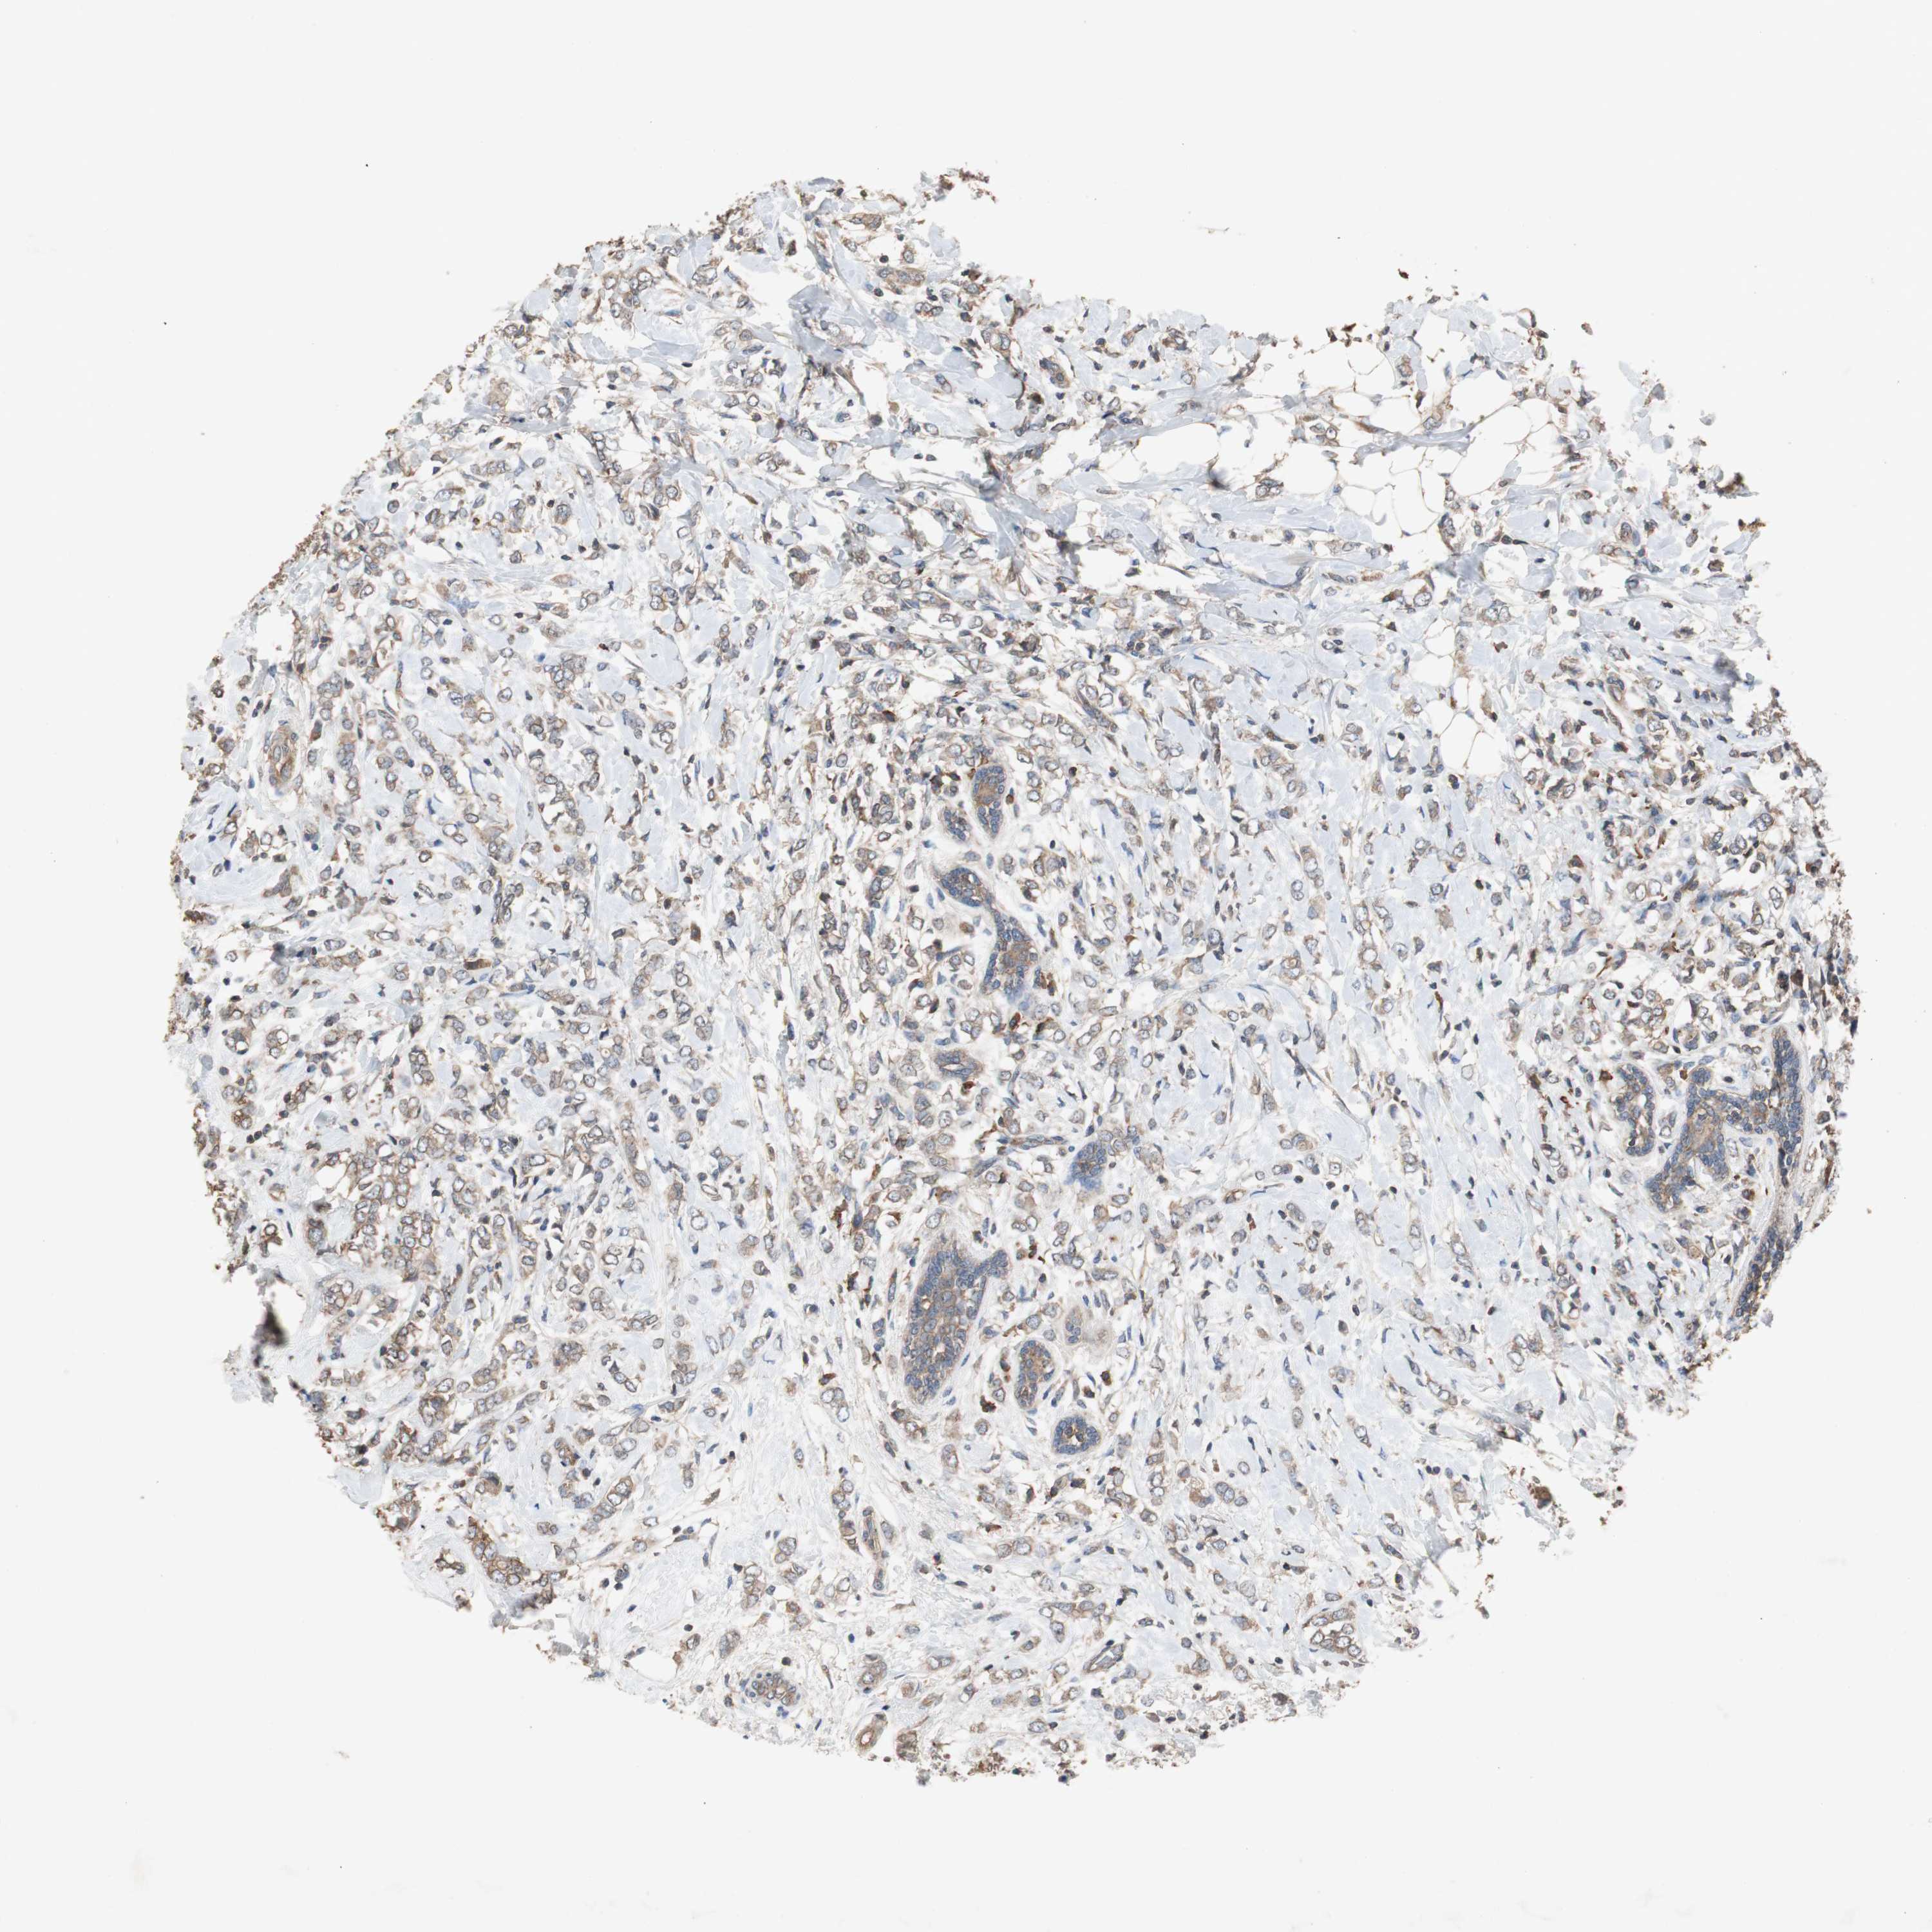

CANCER BREAST CANCER Show tissue menu

BRCA TCGA BRCA VALIDATION PROTEIN EXPRESSION